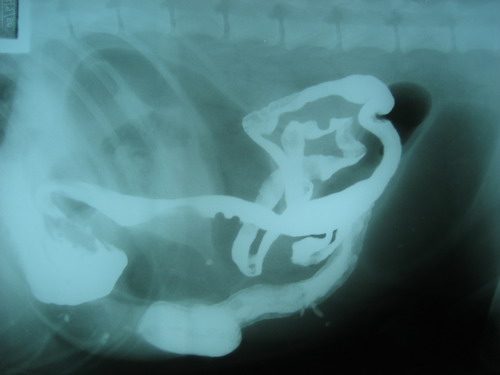

3 วันต่อมา โทรไปเช็คกับเจ้าของพบว่า น้องหมาไม่ทานอีกแล้ว .... ทำอย่างไรก็ไม่ทาน และถ่ายอุจจาระออกมาน้อยมาก ... แต่ยังคงมีเรี่ยวแรง รับแขกได้อยู่ น้ำหนักลงดลงไปกว่า 4 กิโลกรัม ..... สิ่งแรกที่ผมนึกถึงตอนสมัยเรียนวิชารังสีวิทยา ก็คือการป้อนแป้ง Barium ซึ่งเป็นสารทึบรังสีให้กับสุนัข เพื่อดูทางเดินอาหารว่ามีการอุดตันหรือไม่

ประกอบกับประวัติของสุนัขตัวนี้ คือ เจ้าโกลเด้นท์ตัวนี้เป็นหมาที่กินแบบไม่เลือก ตะกละ กินทุกอย่างที่ขวางหน้า โอกาสที่จะมีอะไรไปอุดตันก็เป็นไปได้ (แต่เราก็คลำไม่พบ ให้พี่ๆ หมอช่วยกันคลำก็ไม่เจออะไร และอย่างที่บอกคือ x-ray ครั้งแรกก็มองไม่เห็น)

หลังจากการป้อนแป้งเข้าปากน้องโกลเด้นท์ไป (ป้อนยากเหมือนกัน แป้งเลอะเต็มกางเกงผมเลยหล่ะ ) x-ray ทุกๆ 3 ชั่วโมง ก็จะเห็นแป้งไหลไปตามทางเดินอาหาร ผ่านกระเพาะอาหาร และเข้าสู่ลำไส้เล็กส่วนต้น ...

ผ่านไปร่วมๆ 19 ชั่วโมง แป้งก็ยังคงอยู่ในลำไส้เล็ก ทั้งๆ ที่ความเป็นจริง น่าจะต้องถ่ายออกมากับอุจจาระแล้ว!!! จากฟิล์มเห็นชัดเจนเลยว่า ลำไส้เล็กมีการอุดตัน จะมีอะไรอุดตันนั้น ก็เป็นไปได้หลายอย่างมากๆ แต่สิ่งที่อุดตันนี้แน่นอนว่า ไม่ทึบรังสี จึงทำให้ x-ray ไม่เห็น

บ่ายวันนั้น (ซึ่งล่วงเลยมาเกือบสัปดาห์นับจากวันแรกที่น้องเค้ามาถึง) จึงได้ทำการผ่าตัดเปิดเข้าไปตรวจดู พบว่ามีก้อนวัตถุลึกลับ อยู่ในลำไส้เล็กส่วนปลาย ...